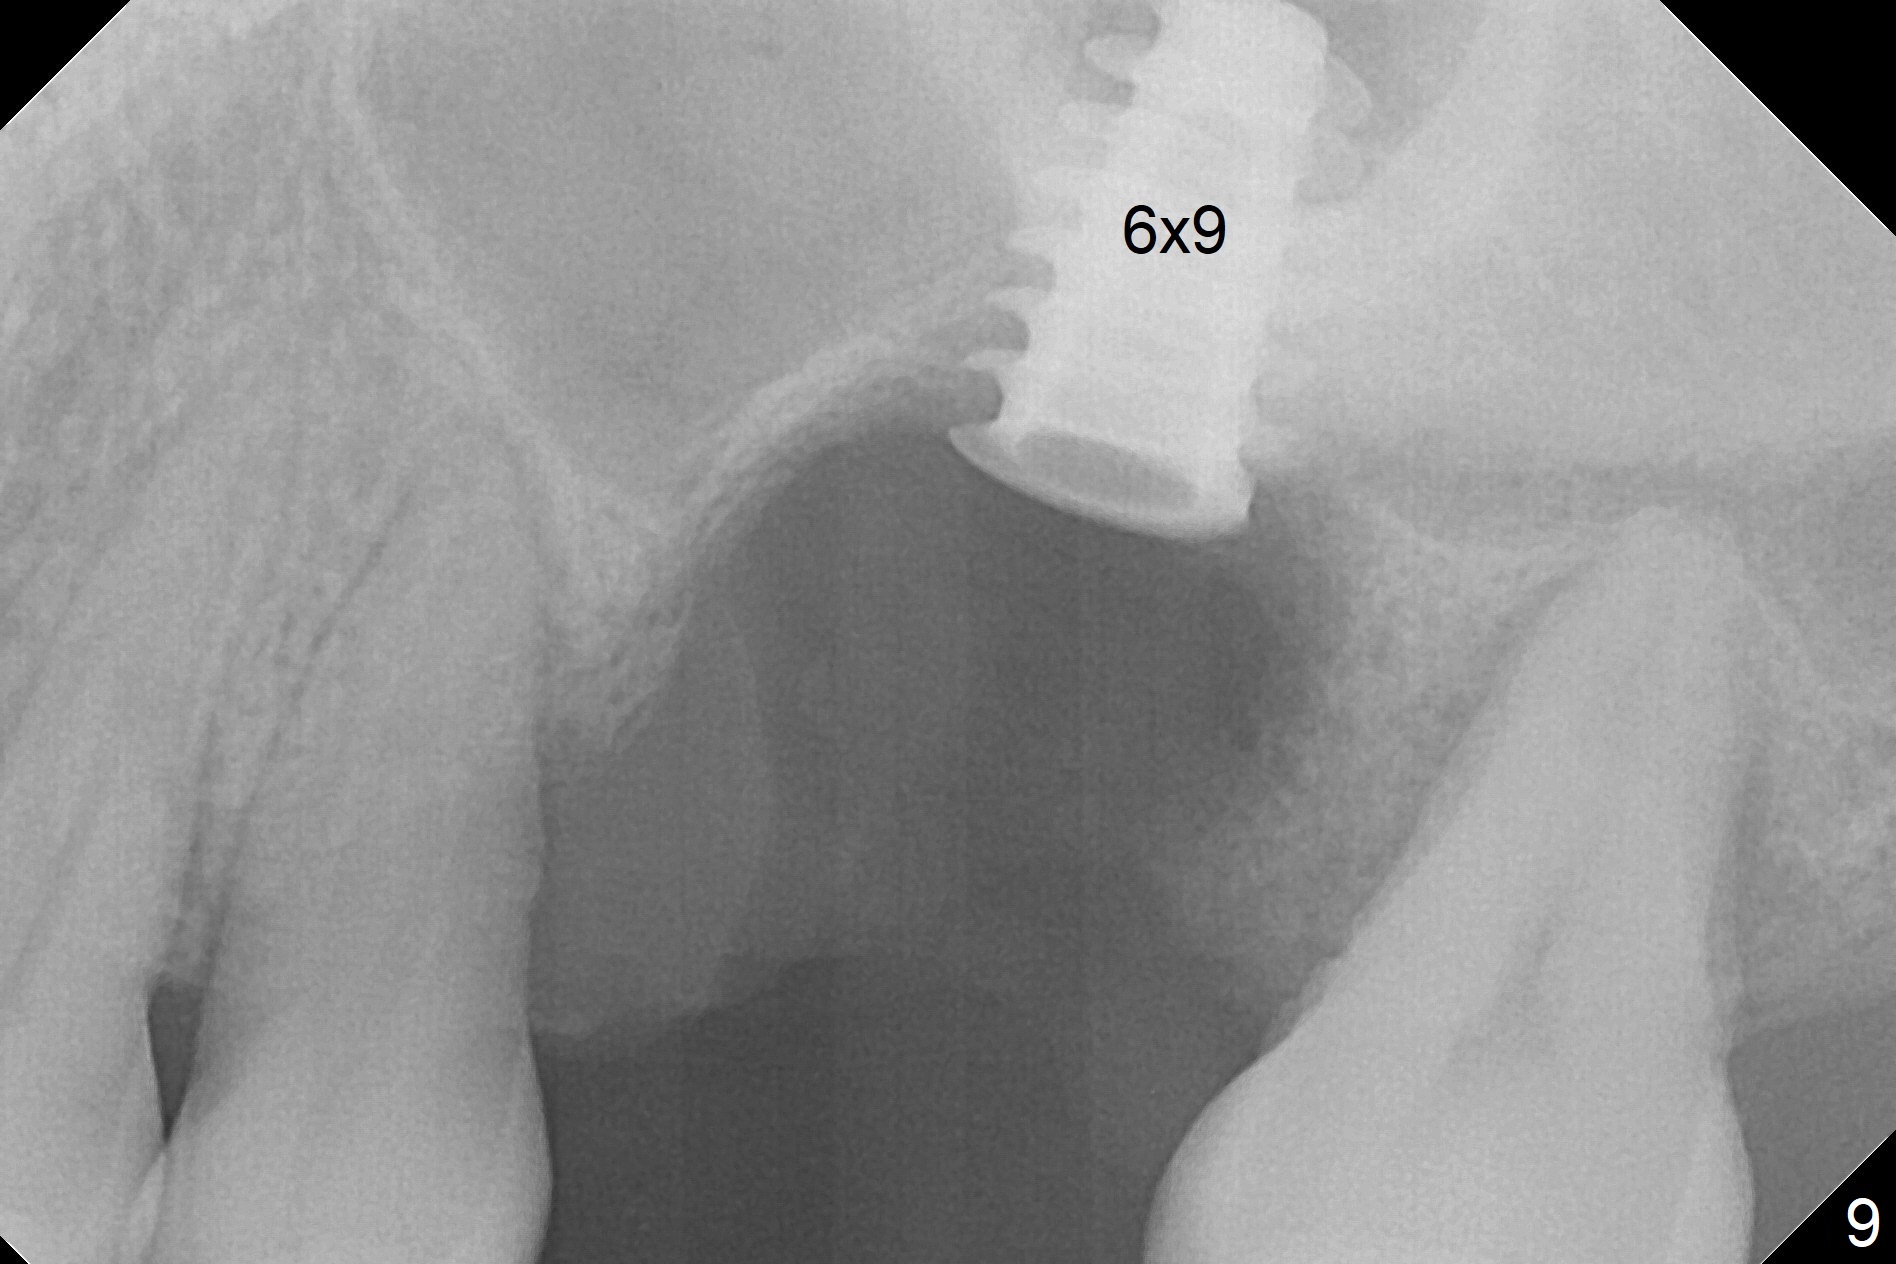

When the displaced tooth #14 (Fig.1) with palatal gingival recession (Fig.2) is extracted, the buccal plate is low, while the palatal one is lost.  Osteotomy is initiated in the bottom of the large socket with Marking Drill.  The bone turns bluish, suggesting thin bone (in fact less than 1 mm as well as low density).  Magic Sinus Lifter (Fig.3 *, Fig.4 blue area) is used for sinus lift (Fig.4 (red curved line: lifted sinus membrane; grey area: a portion of the lifted sinus floor), followed by insertion of a piece of PRF plug and Vanilla bone graft for sinus lift.  The osteotomy is enlarged lightly with 4.8 mm Magic Drill (compare black strips between Fig.4,5).  A 5x9 mm dummy implant (Fig.5 green) is dislodged into the sinus.  The lifted sinus membrane holds the implant in place.  The black thin strip in Fig.5 and black circle in Fig.6a (occlusal view) represents the osteotomy.  After increase in the osteotomy with Lindamann bur (Fig.6b red circle), the implant (Fig.6c green) is retrieved with endodontic forceps (Fig.6c two blue dots (beaks of the forceps); Fig.7,8).  With the enlarged osteotomy (Fig.6d), a 6x9 mm dummy implant is placed deep (Fig.9).  The definitive implant is 6.5x11 mm with insertion torque ~ 15 Ncm (Fig.10).  With placement of a healing screw and further placement of allograft (Fig.11 *), the socket is closed with PRF membrane and collagen plug (Fig.12).